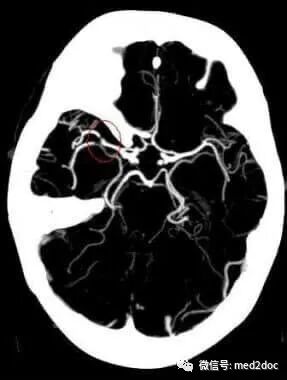

自美国新冠肺炎暴发大流行,也注意到「血栓并发症」,年轻人和中年人突然中风。《新英格兰医学杂志》即将于4月29日在在线发表的一项研究中,纽约市西奈山团队介绍了他们自3月23日至4月7日,报告了5例因新冠肺炎感染2周内引发大血管中风(large vessel stroke)的年轻患者的研究。

研究人员得知这种病毒似乎是通过血液凝结过程引起疾病的感到惊讶。就中风的表现而言,这可能对大血管的影响超过对小血管的影响。研究人员指出,血管壁的炎症可能是血栓形成的驱动因素。该研究报告与其他研究一起指出了这一新现象。

新冠病毒患者大多经历了最致命的中风类型。它们被称为大血管栓塞(large vessel occlusions),因为它们位于主要的供血动脉中,因此可以一击消灭负责运动、言语和决策的大部分大脑。而缺血性中风的特征是大脑区域的血液循环突然丧失,从而导致相应的神经功能丧失。急性缺血性中风是由脑动脉的血栓栓塞或栓塞闭塞引起的。